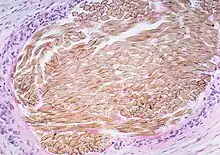

| Picture of a granuloma (without necrosis) as seen through a microscope on a glass slide: The tissue on the slide is stained with two standard dyes (hematoxylin: blue, eosin: pink) to make it visible. The granuloma in this picture was found in a lymph node of a patient with a Mycobacterium avium infection. | |

Macrophages (specifically histiocytes) are the cells that define a granuloma. They often fuse to form multinucleated giant cells (Langhans giant cell).[7] The macrophages in granulomas are often referred to as "epithelioid". This term refers to the vague resemblance of these macrophages to epithelial cells. Epithelioid macrophages differ from ordinary macrophages in that they have elongated nuclei that often resemble the sole of a slipper or shoe. They also have larger nuclei than ordinary macrophages, and their cytoplasm is typically pinker when stained with eosin. These changes are thought to be a consequence of "activation" of the macrophage by the offending antigen.

The other key term in the above definition is the word "organized" which refers to a tight, ball-like formation. The macrophages in these formations are typically so tightly clustered that the borders of individual cells are difficult to appreciate. Loosely dispersed macrophages are not considered to be granulomas.